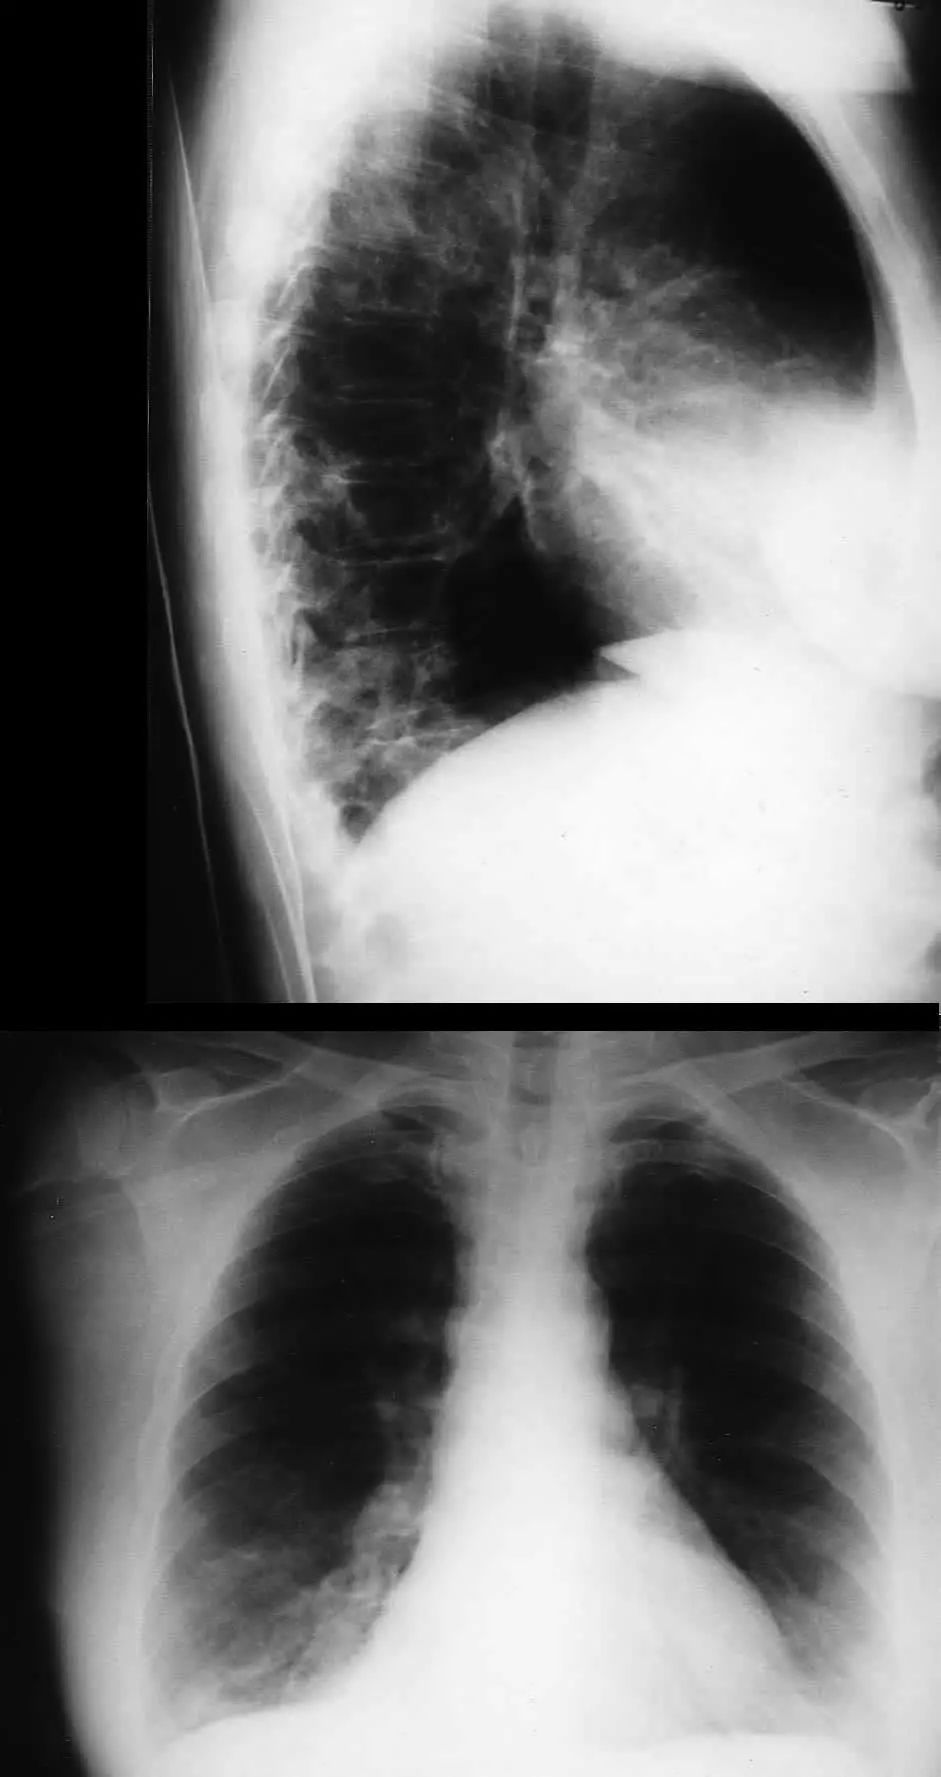

图1.5 40岁肺炎衣原体患者。胸片显示右上、中、下叶多灶性斑片状实变。

图1.6 38岁的支原体肺炎患者。胸部X线片显示左下叶模糊不透明影。